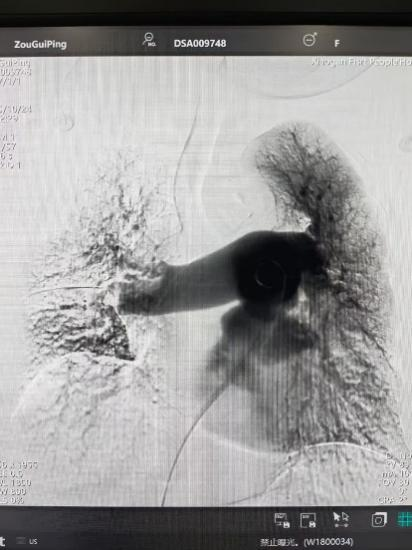

手术前

手术后

手术在局部麻醉下进行。研究人员刺破股静脉,将特制的血栓清除导管精确引导至肺栓塞部位,并利用负压抽吸技术清除大量血栓。然后将溶栓药物精确注射到血栓区域,进一步溶解剩余的残留血栓,恢复肺血液灌注。与此同时,研究人员在患者的下腔静脉中插入了一个过滤器,以防止腿部深静脉的血凝块再次脱落并引起肺栓塞。时间整个手术大约花了一个小时。手术后,邹奶奶的呼吸窘迫症状立即缓解,血氧饱和度明显升高,右心负担明显减轻。他的健康状况正在逐渐好转。